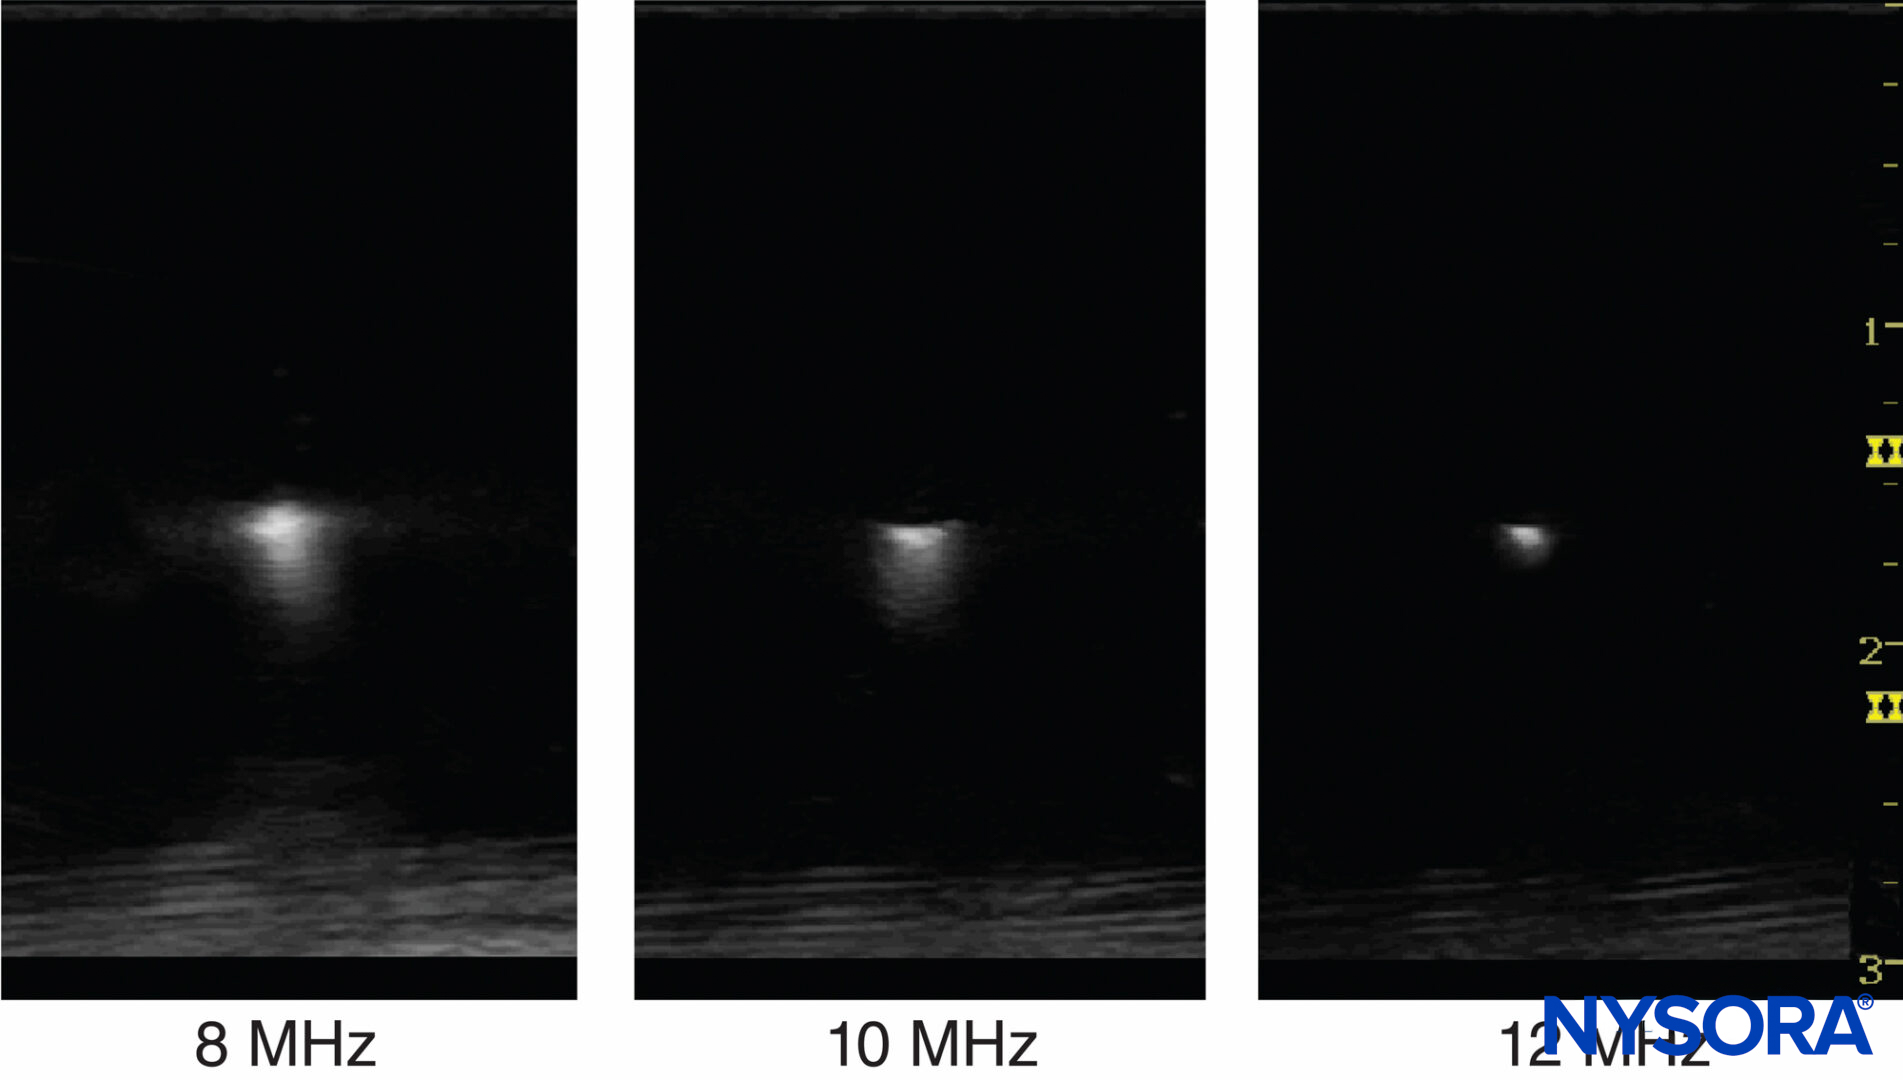

The number of cycles within a pulse is determined by the damping characteristics of the transducer. The number of cycles within a pulse is usually set between 2 and 4 by the manufacturer of the ultrasound machines. As an example, if a 2-MHz ultrasound transducer is theoretically used to do the scanning, the axial resolution would be between 0.8 and 1.6 mm, making it impossible to visualize a 21-gauge needle. For constant acoustic velocity, higher-frequency ultrasound can detect smaller objects and provide an image with better resolution. The axial resolution of current ultrasound systems is between 0.05 and 0.5 mm. Figure 5 shows images at different resolutions when a 0.5-mm diameter object is visualized with three different frequency settings.

Figure 5. Ultrasound frequency affects the resolution of the imaged object. Resolution can be improved by increasing frequency and reducing the beam width by focusing. (Reproduced with permission from Hadzic A: Hadzic’s Peripheral Nerve Blocks and Anatomy for Ultrasound-Guided Regional Anesthesia, 2nd ed. New York: McGraw-Hill, Inc; 2011.)

Lateral resolution is another parameter of sharpness to describe the minimum side-by-side distance between two objects. It is determined by both ultrasound frequency and beam width. The higher frequencies have a narrower focus and provide better axial and lateral resolution. Lateral resolution can also be improved by adjusting focus to reduce the beam width.